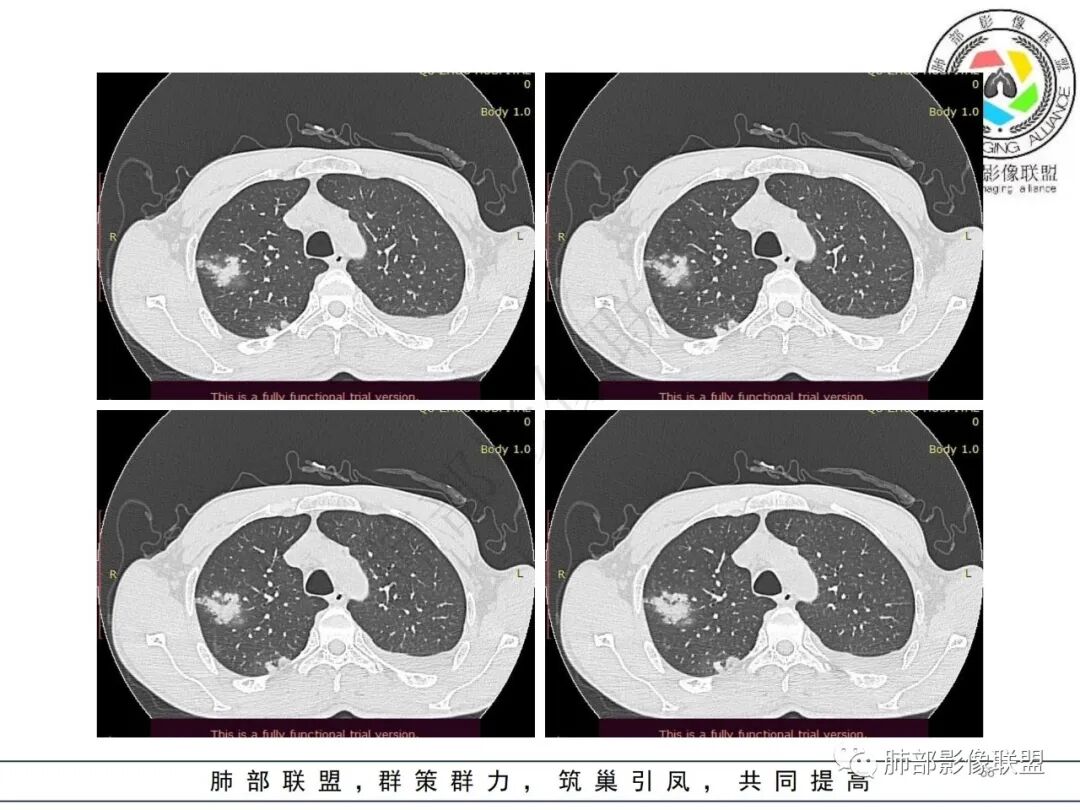

但是肺克肝脓肿血播到肺的,看过很多,没有类似晨读那样表现的,今天晨读不是太典型的血播影像表现;复查的影像就很典型

早上这里是支持血播的

这些层面又像气道

这是比较早的病灶,其他的比较晚的病灶

觉得后面那些符合血道,左下的更符合气道的

从复查分析,按常规左下病灶比其他大,发病早,应该早空洞,更大才对

现在影像反而空洞小,而且早就累及气道,似乎不大符合常规